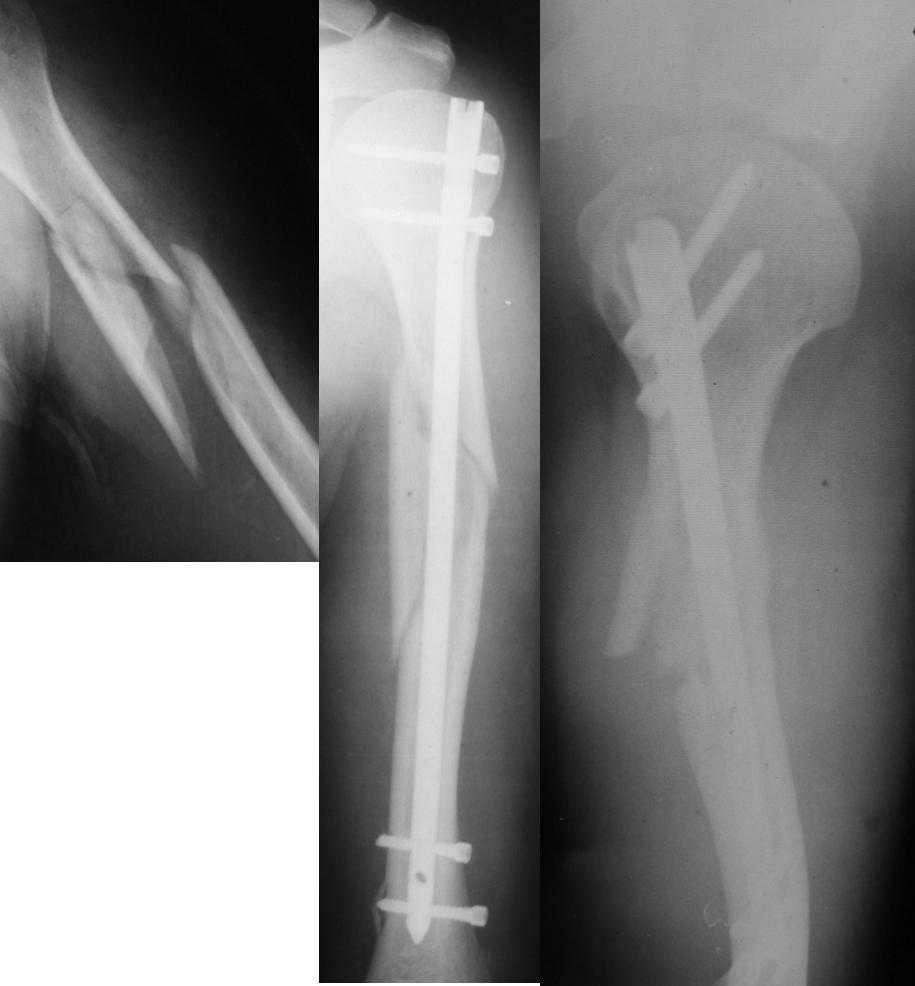

Уважаемые коллеги! Необходима консультация.Больной 52 лет.Травма

02.10.2007г.Операция-19.10.2007г.

Сразу после операции-нарушения кожной чувствительности по наружной

поверхности н\3 предплечья,кисти,1 и 2 пальцев кисти,ограничение

активных движений в луче-запястном суставе при сжатом кулаке.При

электромиографии-лучевой нерв 4% от нормы.Через два месяца после

операции беспокоят боли в месте перелома в покое и при движениях в

плечевом суставе.Отсутствие положительной динамики в восстановлении

кожной чувствительности и объеме движений в л-з суставе.

Дальнейшая тактика-ждать?,оперировать?Спасибо.